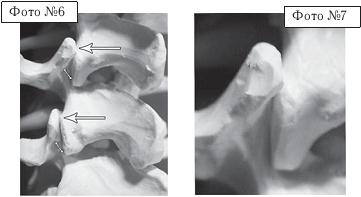

Тракционные методы лечения— вытяжение Слово тракция образовано от латинского слова tracto, что означает «тянуть», «тащить». Проще говоря, это вытяжение (лат. extensio). Вытяжение считается одним из основных ортопедических методов лечения, который применяется при повреждении и заболевании опорно-двигательного аппарата и их последствий. Суть данного метода заключается в том, что с помощью длительной или кратковременной тяги, применяемой в качестве противодействия естественному напряжению тканей, окружающих повреждённое место (к примеру сломанную кость), устраняется смещение отломков при переломе или же оказывается растягивающее действие на ту или иную область человеческого тела с целью устранения деформации или контрактуры (ограничения подвижности). Лечение переломов костей, вывихов суставов с помощью определённых конструкций и аппаратов вытяжения было известно издревле. В своей медицинской практике их использовали такие исторические личности, как знаменитый врач, писатель Древнего Рима Клавдий Гален (II в. н. э.), великий среднеазиатский философ и врач Ибн-Сина (Авицена, XI век), один из выдающихся хирургов Средневековья французский врач Ги де Шолиак (XIV век). Фактически внедрение данного метода в активную практику началось лишь с XIX века, когда известный немецкий хирург, профессор Бернгард Барденгейер опубликовал капитальный труд о повреждениях конечностей, в котором предложил метод лечения переломов посредством вытяжения, сформулировав его основные положения. В травматологии при свежих вывихах, переломах костей метод вытяжения действительно весьма эффективен. Одним из недостатков метода вытяжения при переломе кости считается длительная вынужденная иммобилизация пациента, которая негативно сказывается на его общем состоянии. Тем не менее, ради того чтобы кость срослась правильно, стоит потерпеть такие временные неудобства. Однако если в травматологии при переломах костей метод вытяжения вполне себя оправдывает, то при лечении дегенеративно-дистрофических процессов в позвоночнике (тем более осложнённых протрузиями или грыжами межпозвонковых дисков), как показывает практика, тракционные методы лечения оказываются не только неэффективными, но и усиливающими и ускоряющими процессы дегенерации. Обращаю ваше внимание на то, что применение метода вытяжения при лечении остеохондроза позвоночника — вопрос в научных кругах до сих пор спорный, имеющий много весьма существенных нареканий. Однако об этом, естественно, пациент не услышит ни в современной рекламе про разнообразные методы вытяжения позвоночника (тракционной терапии), ни в самих центрах, где практикуются данные методы. Наоборот, в рекламных буклетах можно прочитать следующее: — «вытяжение позвоночника является эффективным средством лечения смещения дисков, сопровождающегося их выпячиванием»; — «является одним из основных методов лечения неврологических проявлений остеохондроза позвоночника»; — «тракционная терапия позволяет производить безоперационное лечение грыж межпозвонкового диска»; — «вытяжение проводится, в первую очередь, для устранения болевого синдрома». Последнее, как правило, выделяется особым шрифтом, чтобы пациент не пропустил главной зацепки для своего сознания «в первую очередь для устранения болевого синдрома», то есть следствия заболевания позвоночника, и не очень задумывался о причинах возникновения своей болезни и тем более о дальнейших последствиях такого «эффективного лечения». Однако давайте подробнее разберёмся, что такое вытяжение позвоночника, за счёт каких механизмов идёт временное устранение болевого синдрома и к каким последствиям это приводит в дальнейшем. Как вы помните, позвоночно-двигательный сегмент является структурой трёхопорной (межпозвонковый диск и два дугоотростчатых сустава, на которые приходится вся нагрузка от веса вышележащей части тела и мышечных усилий). Чтобы понять суть данного метода, для начала рассмотрим на макете позвоночника, что происходит в процессе вытяжения с межпозвонковым сегментом. ![]() На фото № 4 макета позвоночника наблюдается нормальное взаимоотношение суставных поверхностей в дугоотростчатых суставах. На фото № 5 — нормальное взаимоотношение суставных поверхностей в дугоотростчатом суставе (увеличенный вариант).

На фото № 6 макета позвоночника наблюдается смещение (подвывих) суставных поверхностей дугоотростчатых суставов. На фото № 7 наблюдается смещение (подвывих) суставных поверхностей дугоотростчатого сустава (увеличенный вариант). ![]() На фото № 8 макета позвоночника наблюдается перерастяжение дугоотростчатых суставов вследствие вытяжения. На фото № 9 наблюдается перерастяжение дугоотростчатого сустава (увеличенный вариант). ![]() Фото № 10 На фото № 10 макета позвоночника наблюдается нормальное взаимоотношение суставных поверхностей дугоотростчатых суставов, в норме высота межпозвонкового диска и межпозвонковых отверстий. ![]() Фото № 11 На фото № 11 макета позвоночника наблюдается смещение (подвывих) суставных поверхностей дугоотростчатых суставов. Подобное смещение, как правило, происходит вследствие развития дегенеративно-дистрофических процессов в межпозвонковом диске. При этом уменьшается высота диска, сужается просвет фораминального отверстия (межпозвонкового), что может способствовать ущемлению спинномозговых корешков (нервов) и сосудов. ![]() Фото № 12 На фото № 12 макета позвоночника наблюдается перерастяжение дугоотростчатого сустава вследствие вытяжения, расширение фораминального отверстия, а также растяжение задних отделов фиброзного кольца межпозвонкового диска и сближение вентральных (передних) отделов тел позвонков. Это приводит межпозвонковый диск в клиновидное состояние, что способствует выталкиванию содержимого межпозвонкового диска из передних его отделов в задние. |